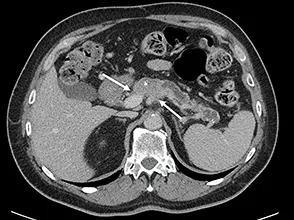

Figure 1 : AP résécable. Absence de contact veineux. Tumeur peu hypodense en scanner ayant nécessité un complément de documentation pancréatique par IRM